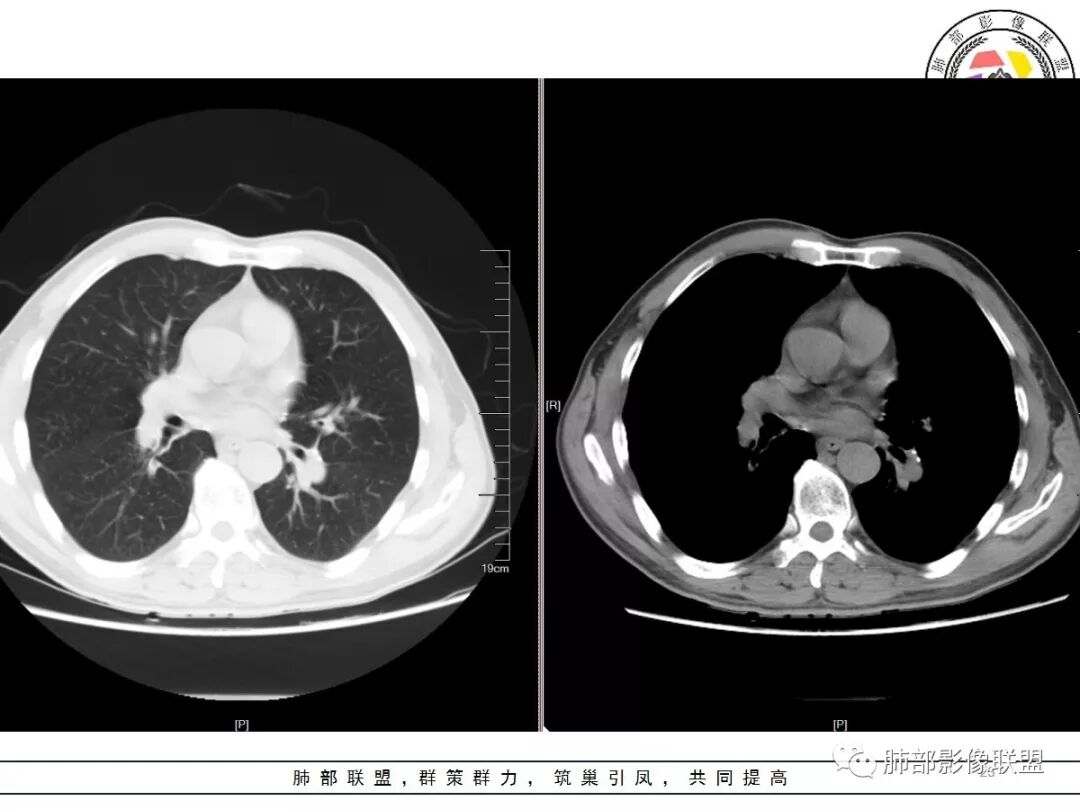

右上肺结节影,有平直收缩有膨隆,有长短毛刺,胸膜牵拉,增强扫描强化不明显或轻度强化,左上肺少许条索斑片状影,强化无特殊,纵隔肺门淋巴结钙化,肺气肿,肺大泡背景,老年男性,首先一元化都考虑结核,右肺上叶结节周围血管稍增粗,需要警惕合并肺癌。

男,57岁;图像质量好,1.25*10层=12.5mm,两个病灶,形态奇特,毛刺长,强化静脉期最高,增强稍微中心密度低一些,肺尖部位;

诊断:结核(多灶,2;多态,中心低、边界稍高);部分,肺尖;毛刺,长,非真正毛刺。

老年男性,体检发现右上尖段及左上尖后段不规则结节影,右上尖段结节边缘长毛刺、似见卫星灶、局部胸膜牵拉,增强无明显强化。左上结节环形强化,考虑结核。老年男性,肺气肿背景,注意排除右上肺腺癌。

右肺上叶尖段结节,边缘平直收缩,周围有细长毛刺,有卫星灶,符合结核,但有静脉期轻度强化,结核应该没有强化,肺癌?

彭君:

双肺尖结节 左肺边缘收缩 环形强化 右肺病灶上部边缘平直及长毛刺 下部分边缘膨隆及分叶 细短毛刺 好像有局灶强化 不除外结核基础上的瘢痕癌可能

倾向二元,左肺上叶病灶环形强化支持结核,右肺上叶结节平直、部分稍膨隆,胸膜牵拉征,部分毛刺粗短、支气管似乎边缘截断,临近小叶间隔增厚,延迟强化,密度似乎不均匀,内见小点状坏死,腺癌放前面,炎性放待排。